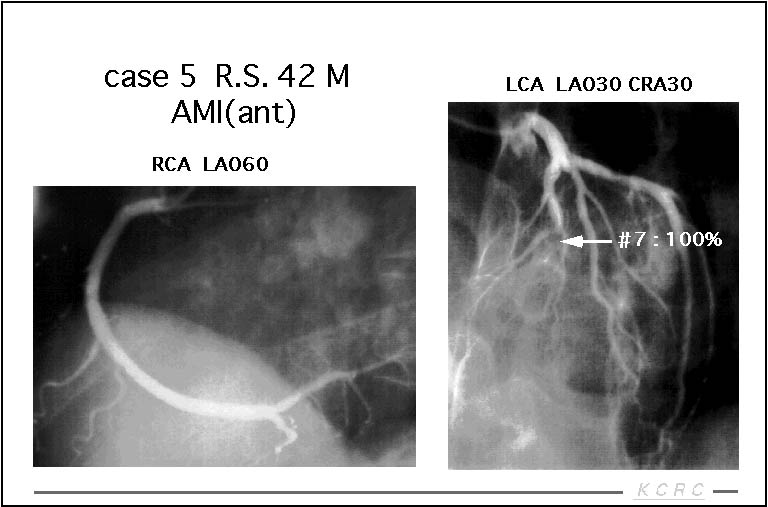

症例を呈示します。胸痛があり冠動脈造影を行った結果、LADに50%の狭窄を認め、虚血の有無の評価の目的でシンチを行いました。

【スライド7】

負荷像、安静像とも血流の低下は認められず、内服治療で経過観察となりました。

症例2、前壁の陳旧性心筋梗塞の症例です。冠動脈造影の結果、LADは完全閉塞。RCAにも50%の狭窄を認めたため、LAD領域のviability評価とRCAの虚血評価の目的でシンチを行いました。

【スライド9】

前壁中隔から心尖部はdefectであり、LAD領域のviabilityはないものと判断。RCA領域の虚血は認められず、この症例も経過観察となりました。

他の核種を用いた症例を示します。前壁の急性心筋梗塞の症例です。冠動脈造影ではLADに完全閉塞を認めます。